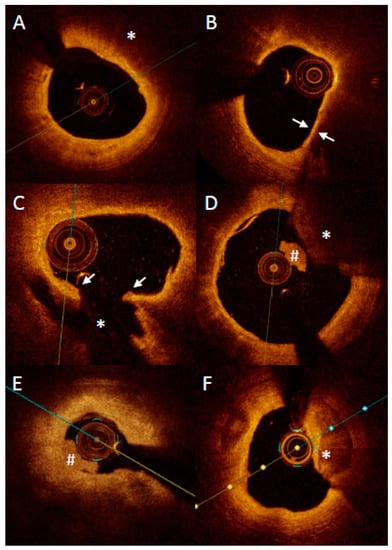

The initial studies presented the identification of long lipid and severely vessel narrowing lesions on OCT-identified patients at increased risk of MACE [61]. Recently, a published study, a COMBINE OCT-FFR trial, presented that the identification of TCFA in diabetic patients increased almost five times the risk of MACE at 18-months follow-up despite the absence of ischemia (Figure 5) [38]. This was the first trial shifting the concept of patients’ risk stratification from ischemia to plaque morphology. Importantly, a new subanalysis shows that not any lipidic plaque but only TCFA is related to future MACE, while ThCFA has very benign outcomes comparable to non-lipidic plaques. Comparable results were presented by Kubo et al. in a prospective study in which only lipid plaques were the cause of ACS during 6 years follow-up [62]. What is more important, ACS arose more frequently from lipid plaques with TCFA as compared to those with ThCFA (19% vs. 2%; HR 10.41 (95% CI: 6.48–16.73). Moreover, lipid-rich plaques (defined as lipid arc > 180 degrees) were also independent predictors of ACS. When combing both lipid-rich plaque and TCFA, those two features of plaque vulnerability were present in one third of all plaques, which caused ACS during the follow-up period. Intrudingly, macrophages were not predictors of future ACS events. On the contrary, in a CLIMA study, not only lipid-rich plaque and TCFA were predictors of major coronary events but also macrophages were associated with increased cardiac death or target vessel myocardial infarction. Discrepancy in those studies in regard to macrophages may be explained by subjectivity in the detection of macrophages and different criteria for cardiac endpoints. Regardless, it should be emphasized that macrophages are correlated with inflammation, which was found to be strongly associated with plaque vulnerability both in pathological and in vivo studies.

Figure 5.

Representative case of vulnerable plaque progression. (A) Thin-cap fibroatheroma (TCFA) located in a short lesion in left anterior descending, diameter stenosis 62%, FFR baseline 0.86. Presence of a TCFA 3–6 o’clock adjacent to a healed plaque 12–3 o’clock. (B) Same lesion 13.5 months later when patient presented with non-ST-elevation myocardial infarction and underwent revascularization.

While TCFA remains the cornerstone feature of vulnerable plaque studies, other plaque morphological characteristics, such as healed plaque, have recently also evolved as being at risk for future adverse events [61,69]. Recent insights from the COMBINE trial show that TCFA lesions that progressed to MACE were frequently located adjacent to healed plaque within the same lesion. Treatment modalities for this type of plaque remain to date unknown.